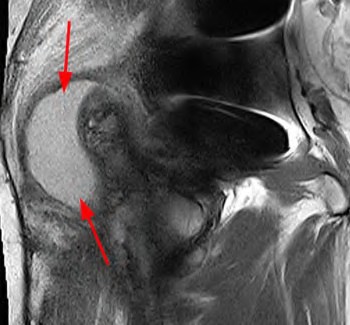

A 72-year-old female presents with progressive left thigh and knee pain for the last year. 5 years ago she sustained a femoral neck fracture treated with the implant seen in Figures A-C (current radiographs). The thigh pain is worse with weight-bearing. C-reactive

protein and erythrocyte sedimentation levels are within defined limits. Which of the following is the most likely cause of her pain?